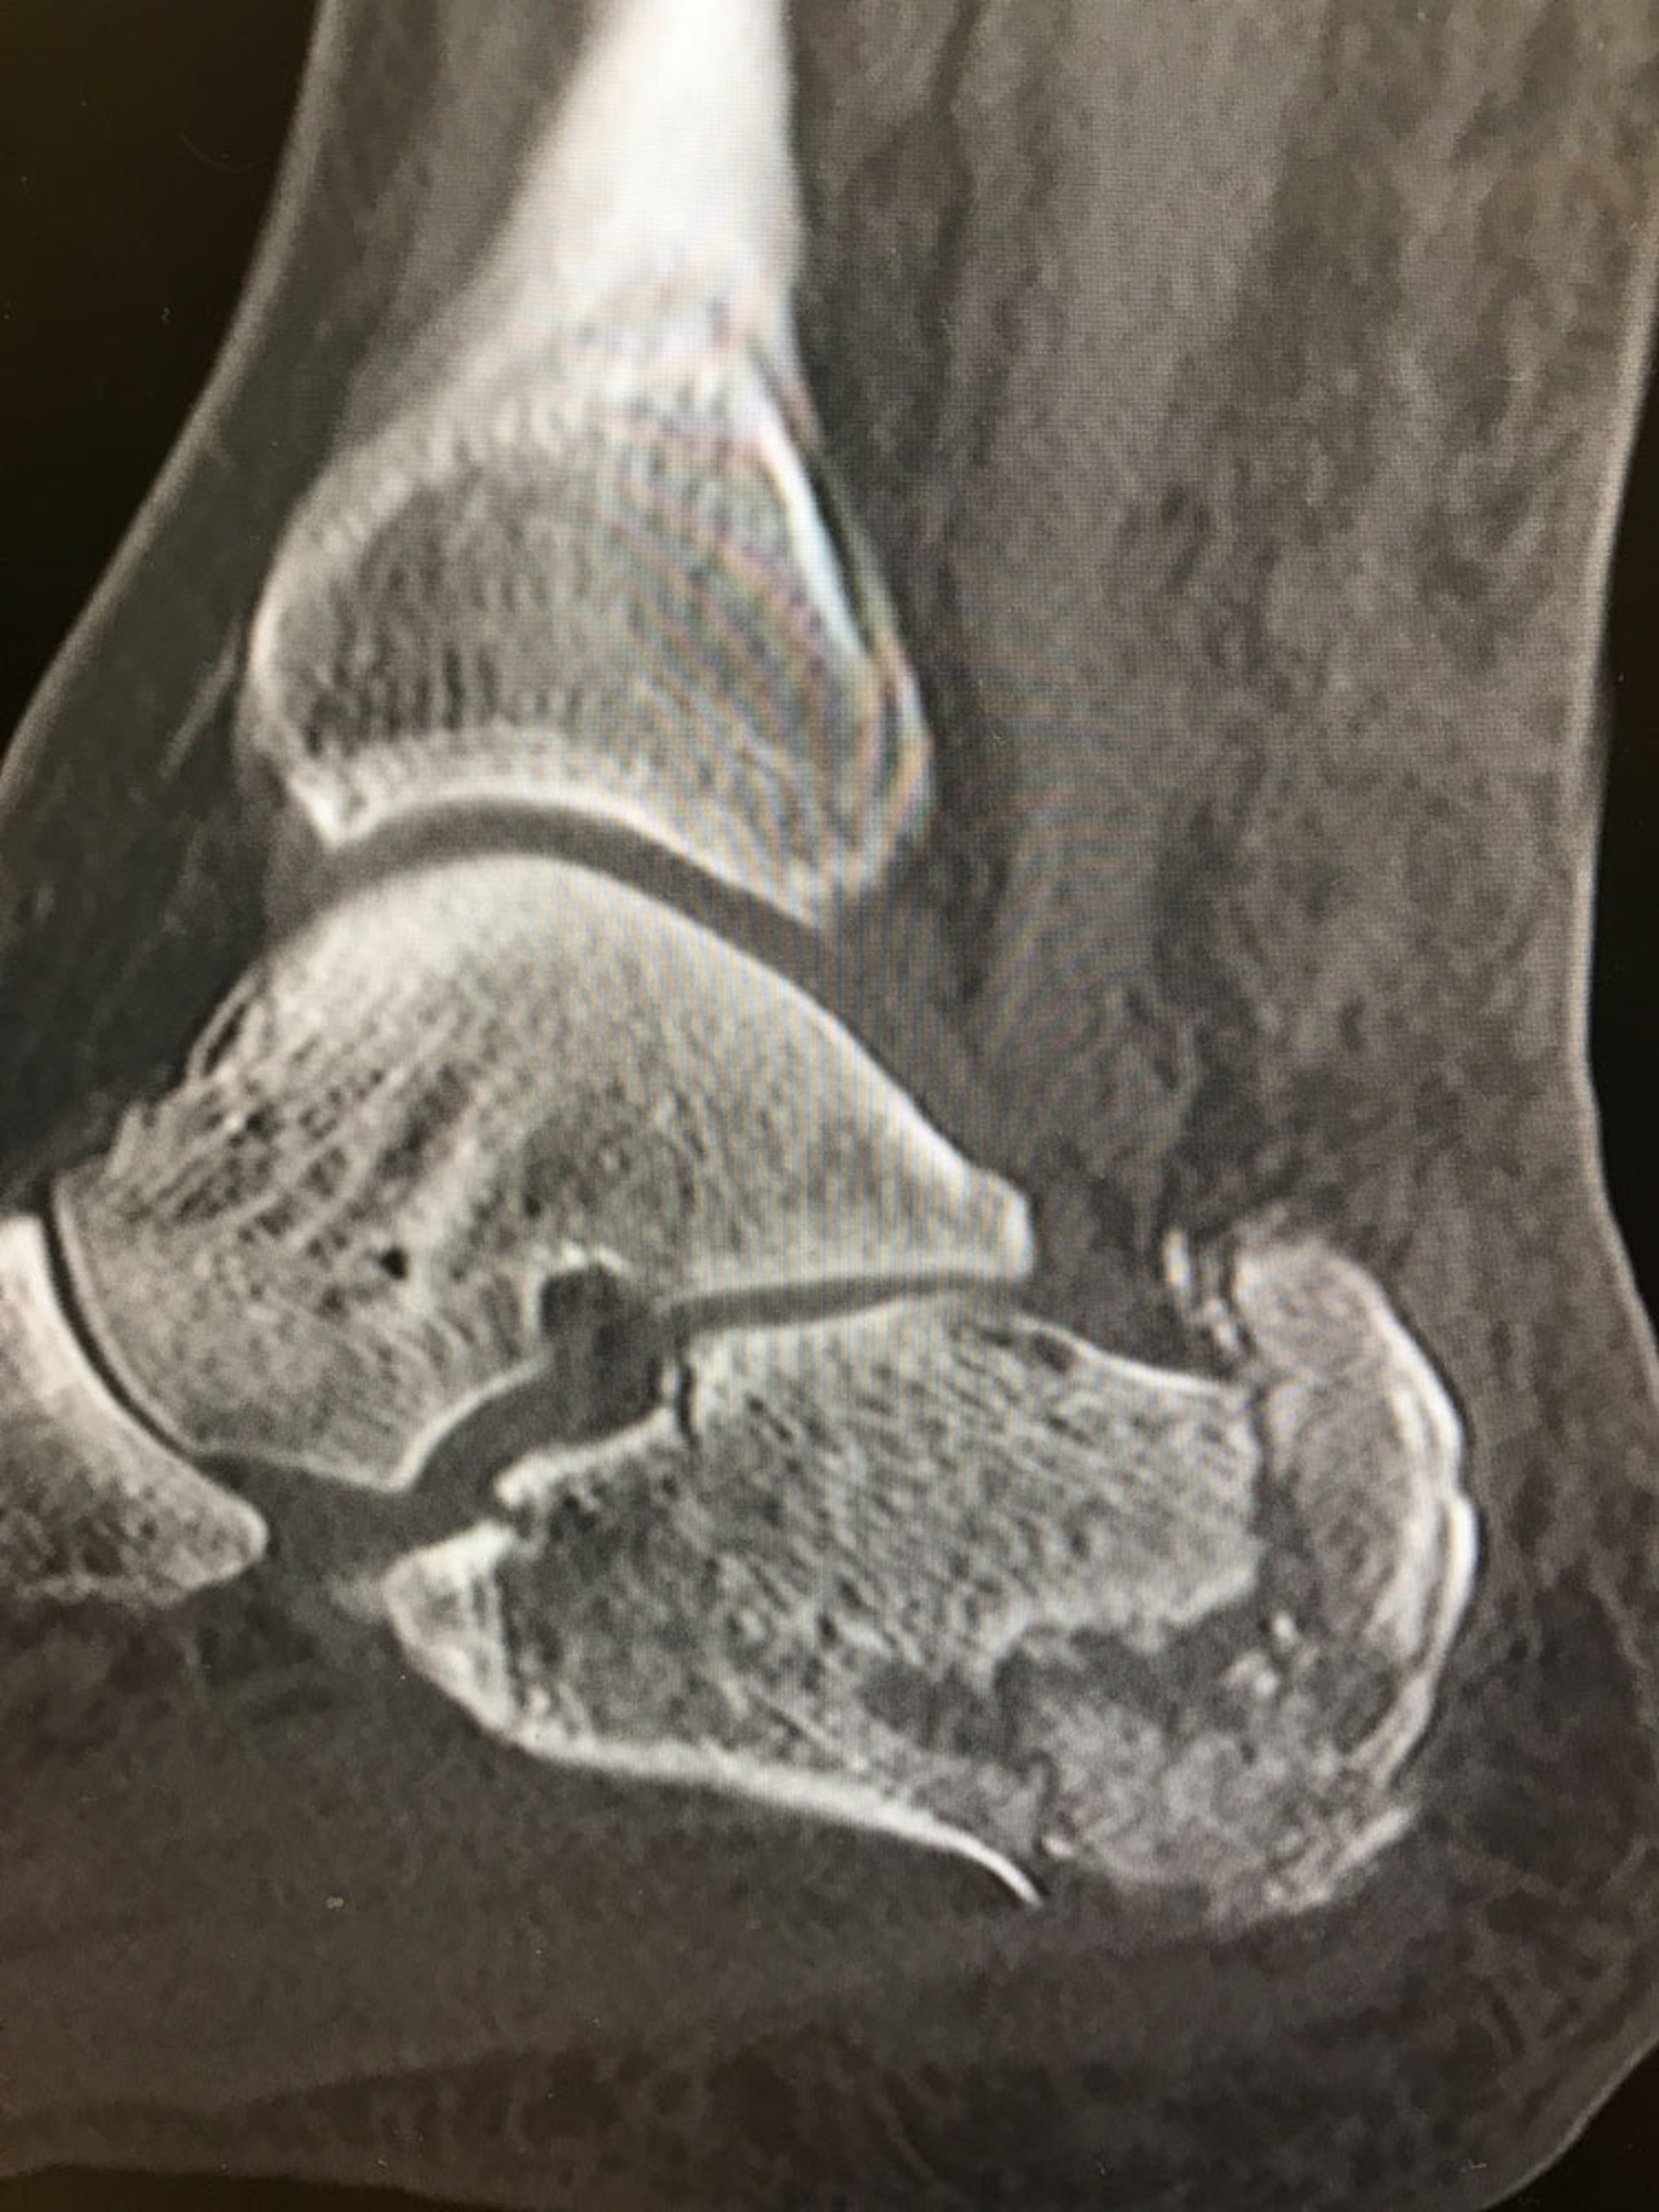

Questa radiografia mostra una frattura comminuta del calcagno.

Image courtesy of Danielle Campagne, MD.